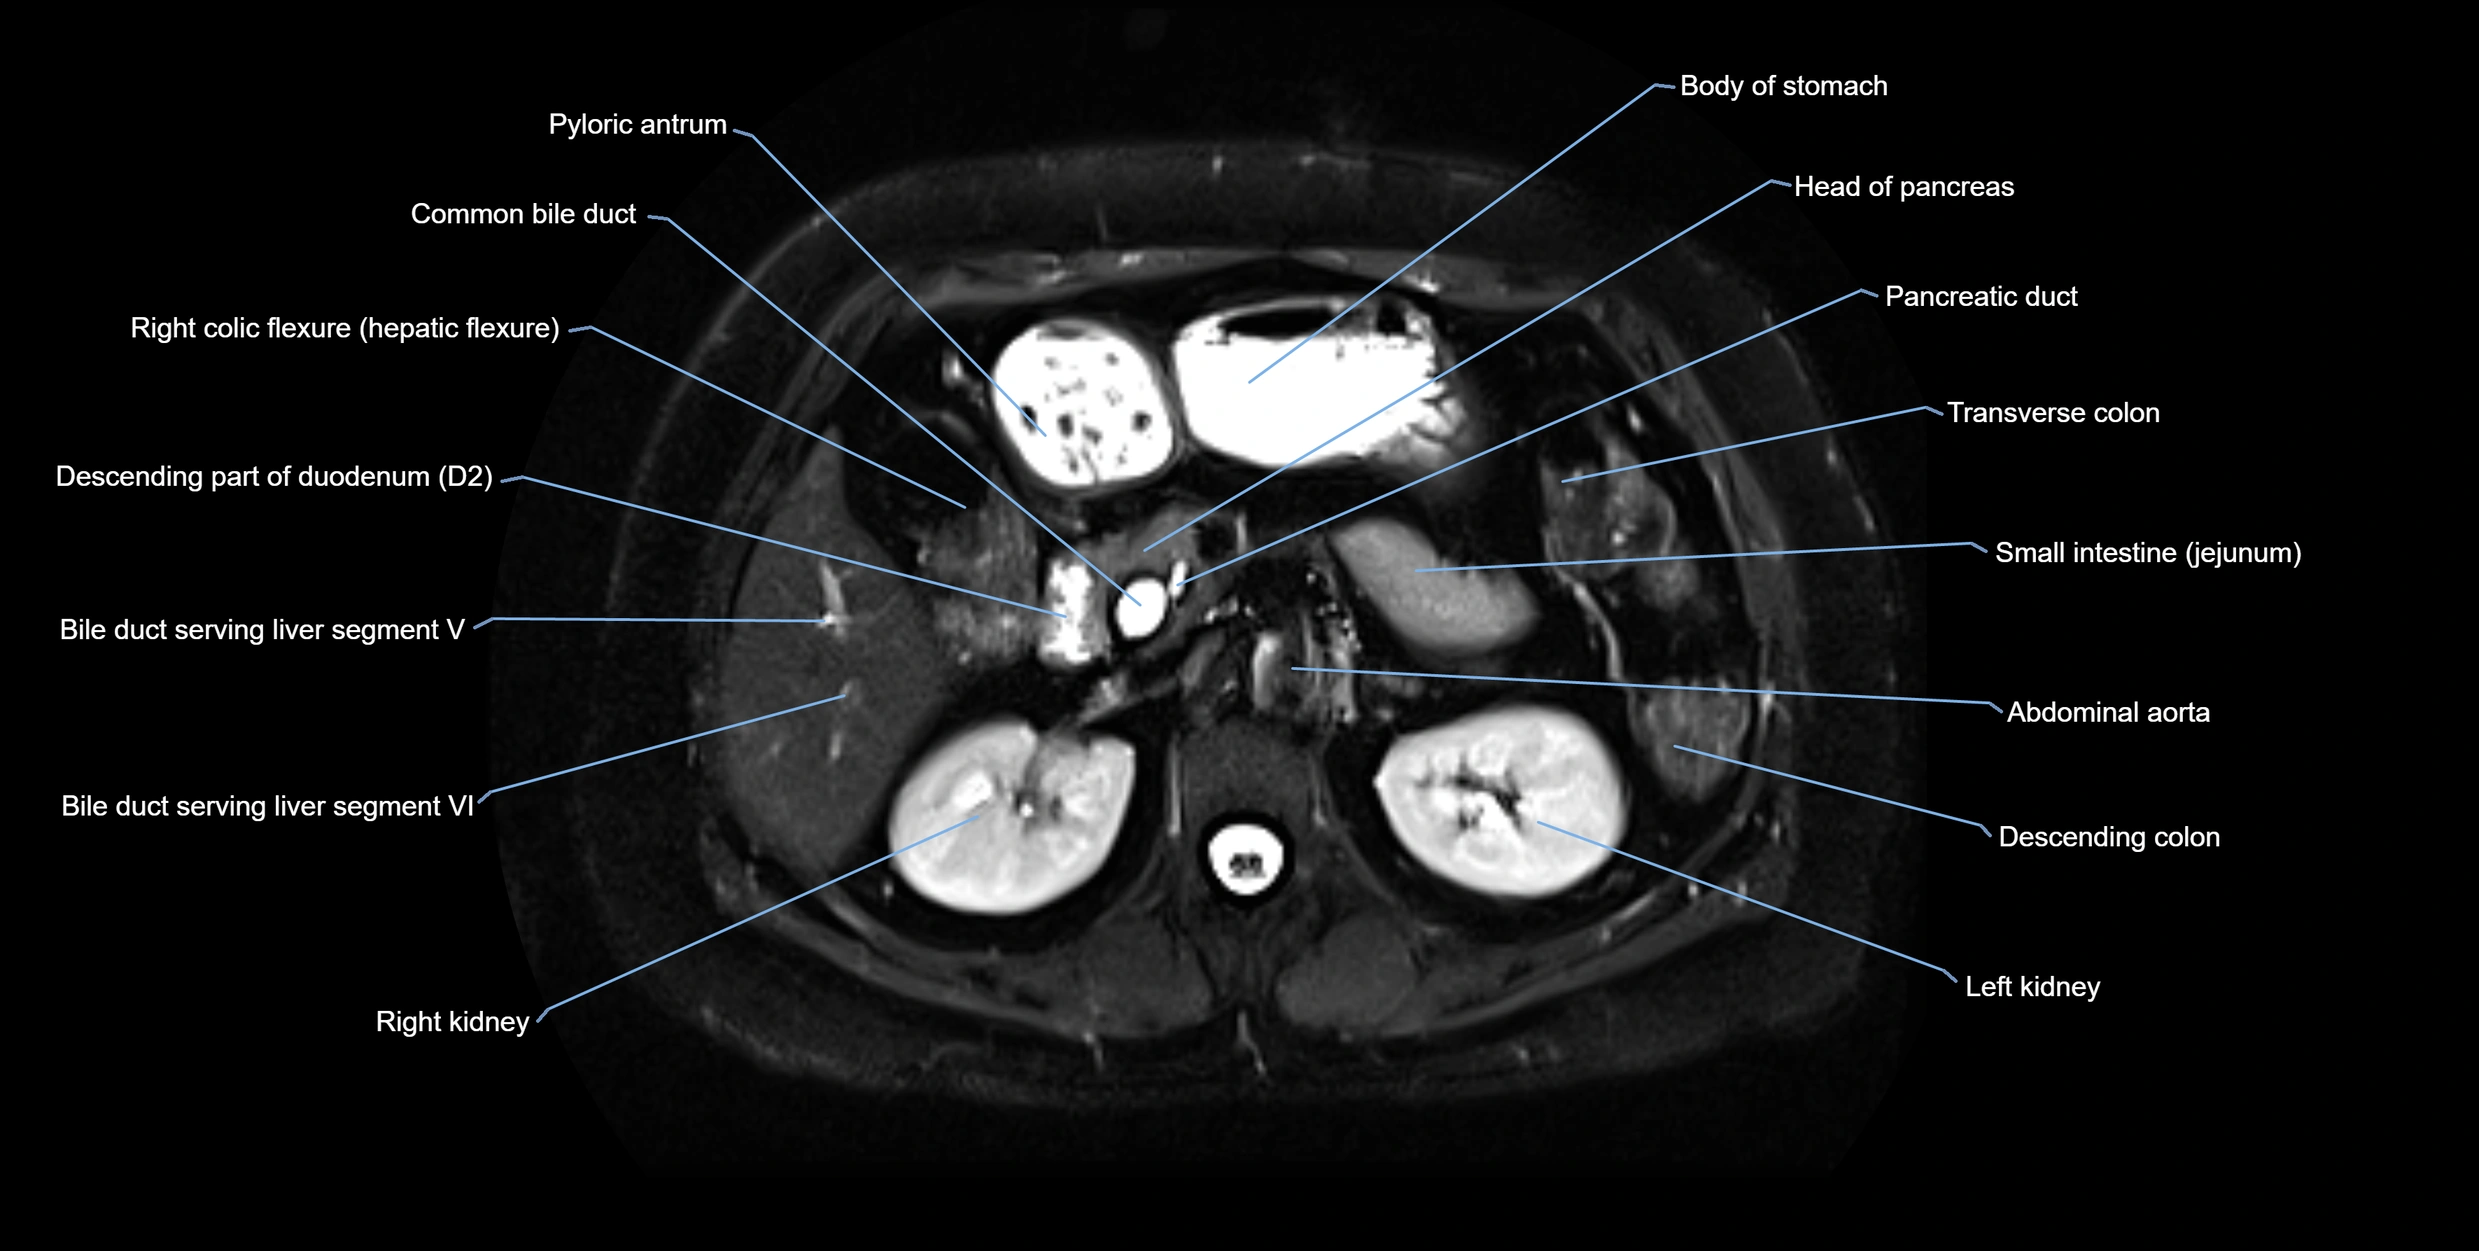

CT Appearance

Non-Contrast CT:

• Normally not visible unless dilated

• Appears as a fine low-attenuation tubular structure in pancreatic head when dilated

• Calcified stones may be detected if present

Post-Contrast CT:

• Duct lumen remains unenhanced, surrounded by enhancing pancreatic parenchyma

• Dilatation or obstruction becomes more conspicuous

• Tumor or inflammatory mass may cause ductal cut-off or narrowing